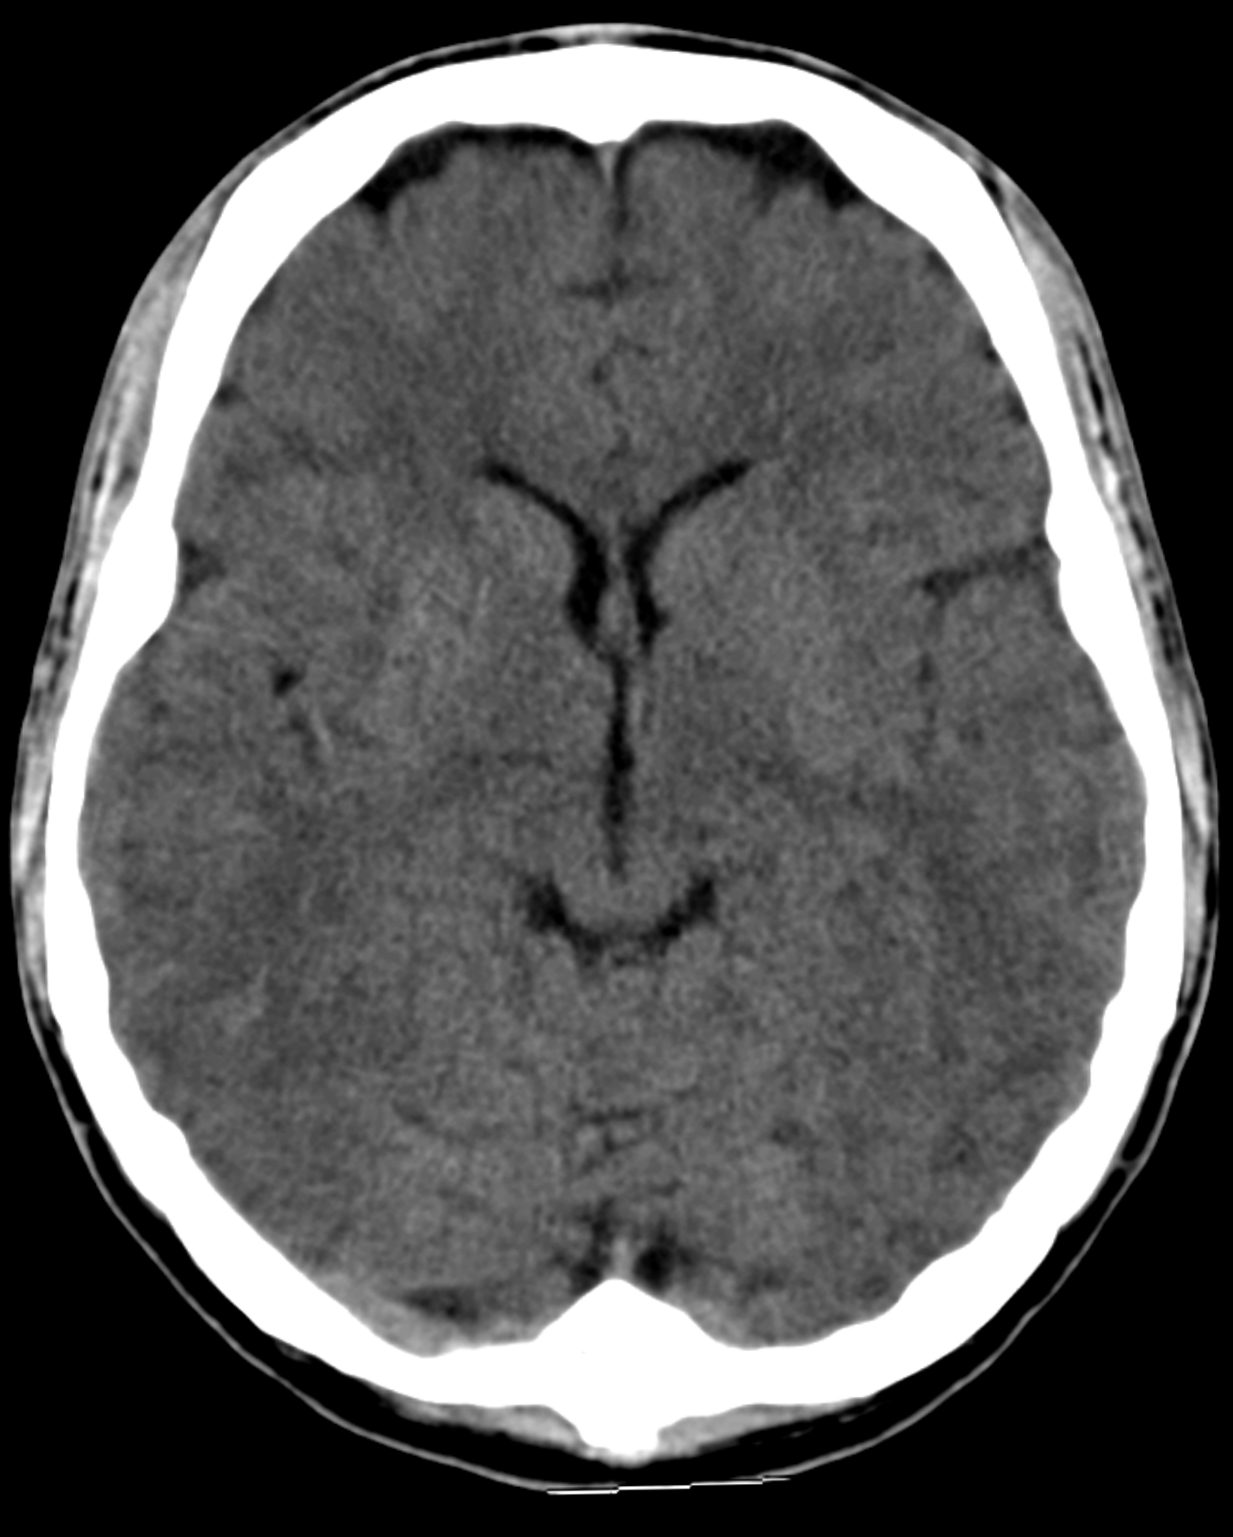

Low Dose CT

Our advanced low-dose multi-slice CT scanner provides highly detailed 3D images that help detect and assess a wide range of conditions with precision. Using the latest dose optimisation technology, we capture exceptional clarity while minimising radiation exposure — so you can have confidence in both your results and your safety.

Low Radiation, High Precision

Your safety is always our priority. That’s why our CT scanner is designed with advanced low-dose technology that significantly reduces radiation exposure while maintaining the highest standard of image clarity. With every scan, we achieve detailed, diagnostic-quality results — without compromise to your comfort or well-being.